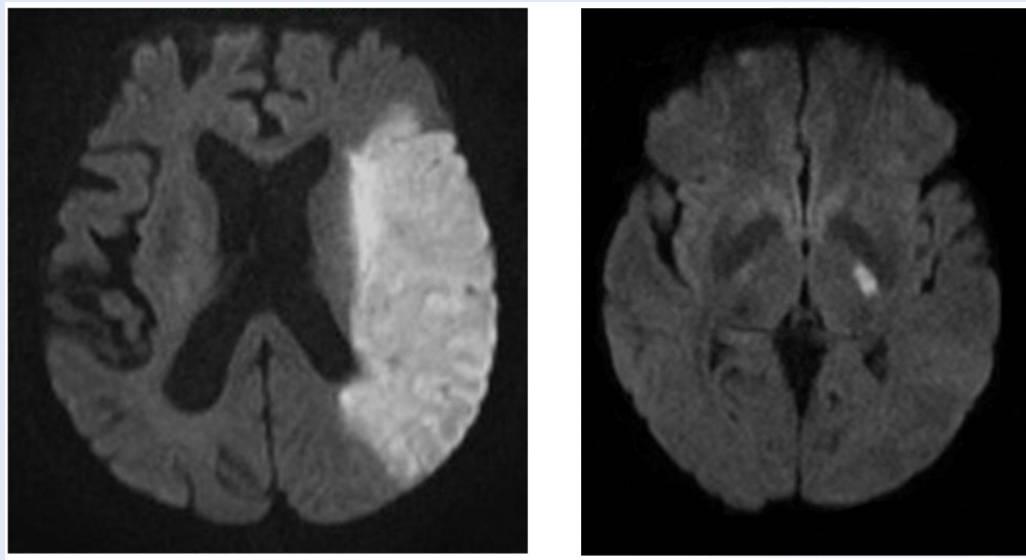

At the Bayview Stroke Intervention Clinic (BaSIC), patients are seen for follow-up at 1, 6, and 12-months post-infarct. Many of these patients have relatively small strokes, as shown on the right image in these brain MRI scans. Patients with a stroke of this size typically lack major motor and language impairments and can appear as though they are fine. However, during their clinic visits, patients with these “small” strokes often express feeling very fatigued, inattentive, unable to concentrate, cognitively slow, etc. While they may not have a visible disability, they still struggle to return to work and normal life due to this cognitive dysfunction.

As part of our research, we are interested in higher level cognitive processes such as attention and multi-tasking. Even after small strokes, these activities can become impaired. This results in the inability for previously high-functioning individuals (school teachers, musicians, CEOs) to re-integrate into their prior home and workplace environments. It results in divorce, loss of jobs, and poor quality of life. The cognitive difficulties seem to occur regardless of the location of the stroke, and the underlying cause is poorly understood. It may be because the brain functions as a network (in other words, you require all of your brain to be functioning normally to be at your best). In order to determine if this is the case and how connections change after stroke, we are partnering with the University of Maryland to determine what is happening in the brain to impair cognition. Eligible patients with small strokes and difficulty with cognition on testing in our clinic travel to our partnering institute where they undergo magnetoencephalography (MEG). Similar to an MRI, the MEG records which areas of the brain are active during various activities. Testing is performed about 1 month after stroke and repeated at 6, 12, and 24 months. Our preliminary data are exciting! A 42-year-old executive presented to clinic with a small stroke, slow processing speed, and poor executive functioning that prohibited him from returning to work and leading meetings. The stroke itself did not explain his symptoms, but MEG showed diffuse abnormal activation within the frontal lobes, an important area for higher level processing (see left figure). These findings indicate that our hypotheses may be correct, but larger studies are needed. If we can determine the brain changes responsible for post-stroke cognitive impairment, we will be able to predict who is most likely to recover, devise better treatment strategies, and promote faster and fuller recovery after stroke.